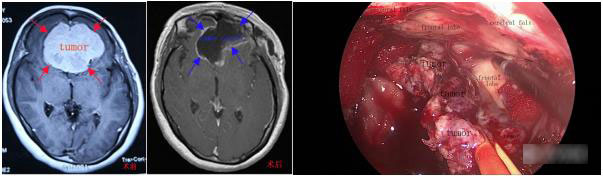

病例1:全神经内镜下经颅切除前颅窝底巨大嗅沟脑膜瘤